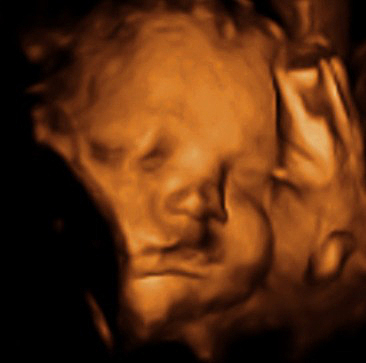

• Semana 19

19

Semana 19

-El sistema nervioso central se empieza a desarrollar rápidamente, sobre todo aquellas áreas destinadas a los sentidos del gusto, el olfato, la audición, la visión y el tacto (Algunos estudios indican que el bebé ya puede oír).

-Empiezan las etapas de sueño y de actividad.